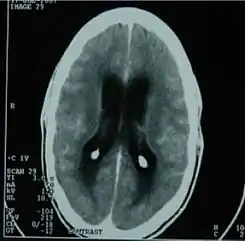

![]() TAC del cerebro mostrando una meningitis tuberculosa. | ||